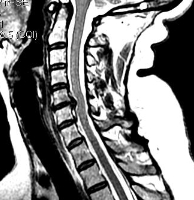

МРТ. Т2-зависимая томограмма. Сагиттальный срез. Грыжа диска.

При шейном остеохондрозе грыжи не приводят к головным болям, они вызывают корешковый синдром, приводящий к болям и неприятным ощущениям (парестезии, слабости) в руке со стороны грыжи. Редко грыжа сдавливает спинной мозг или нарушает кровоснабжение его участка, приводя к миелопатии. Головные боли при остеохондрозе обусловлены нестабильностью в шейном отделе и болезненным напряжением мышц.